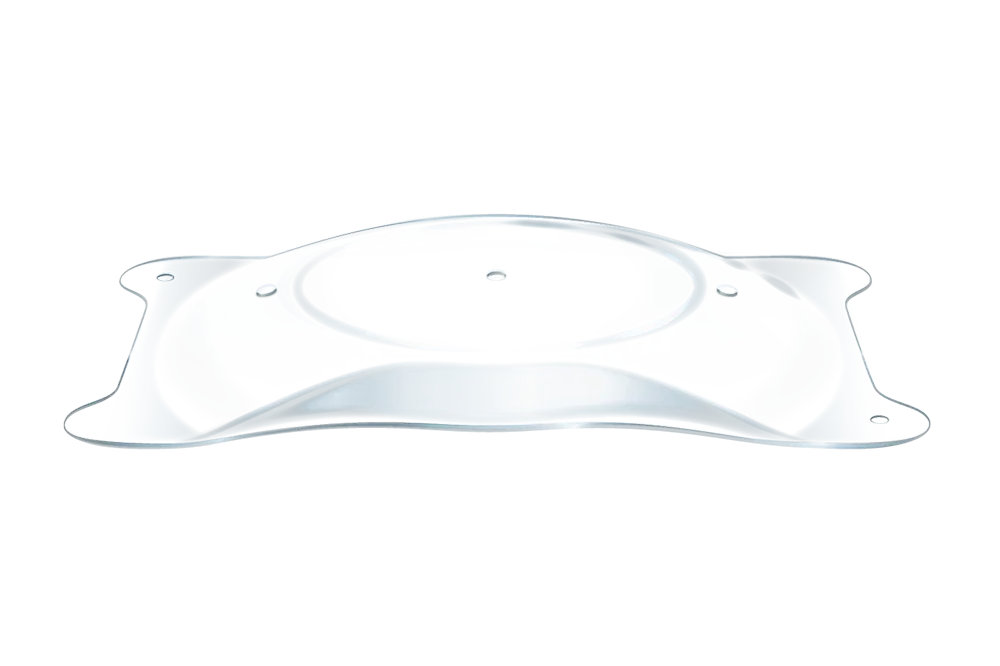

- EVO ICL is een phake lens.

- EVO wordt direct achter de iris en vóór de natuurlijke kristallijne lens geplaatst.

- De toevoeging van de centrale aqua port bij EVO vergemakkelijkt de stroom van aqueous humor doorheen de lens.

- De EVO-lens is een reversibel implantaat.